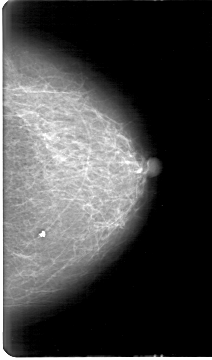

D_4170_1.RIGHT_MLO

LEFT_MLO LINES 5281 PIXELS_PER_LINE 3421 BITS_PER_PIXEL 12 RESOLUTION 43.5 NON_OVERLAY